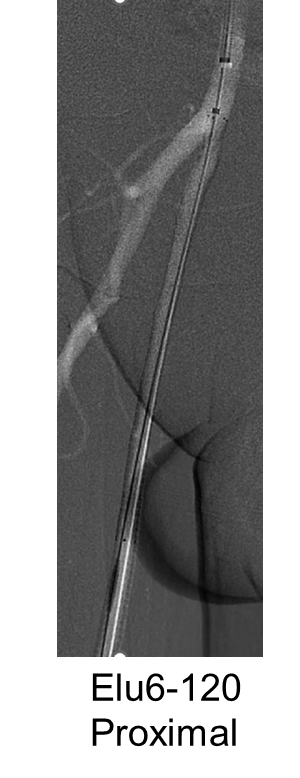

支架植入:遵循“由远及近”原则,先放置远端 DES,再覆盖中段 VB,最后处理近端。利用 Eluvia 的可调节性优化重叠。

后扩:常规使用 6mm 高压球囊进行后扩张,确保支架充分贴壁和管腔获得。